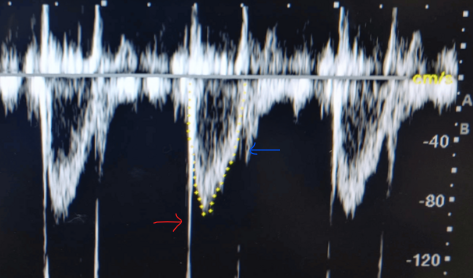

What could cause a high EPSS (>5mm)?

dilated LV

mitral stenosis

aortic regurgitation

In an M-mode tracing of LV basal wall in PSLAX, list the measurements made and describe how to measure them

MV

cursor at the mitral valve leaflet tips

E point septal separation - space between the anterior leaflet and anterior LA wall